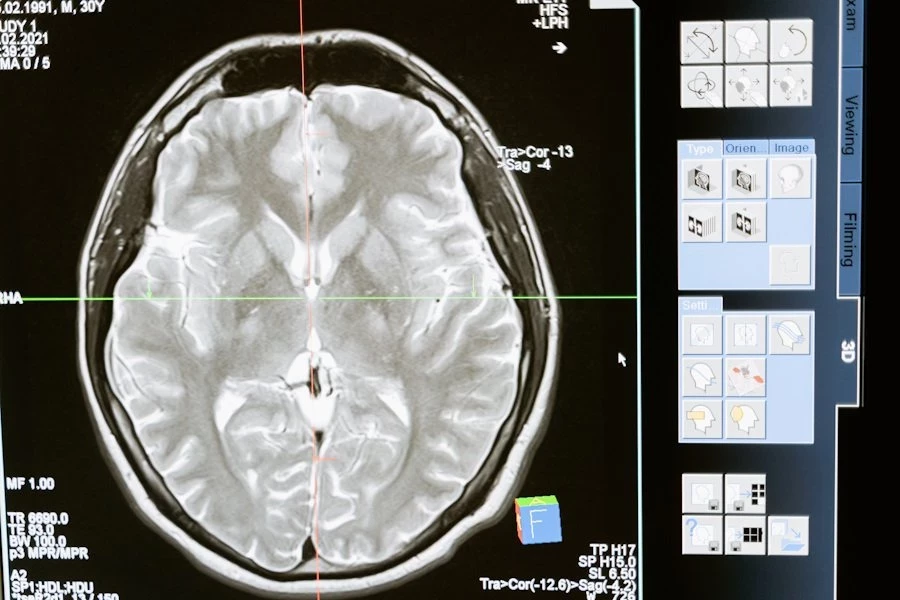

Фото из открытых источников

Ученые из University of Pennsylvania (США) выяснили, что мужчины и женщины по-разному реагируют на полную анестезию, и это связано с физиологическими особенностями организма. Исследование, опубликованное в Neuroscience, показало, что женщины возвращаются в сознание после наркоза значительно быстрее, чем мужчины.

В эксперименте приняли участие 30 здоровых добровольцев обоих полов в возрасте от 22 до 40 лет. Испытуемым вводили изофлуран — популярный ингаляционный анестетик, используемый во всем мире. Ученые следили за изменениями мозговой активности с помощью электроэнцефалографии (ЭЭГ), фиксируя показатели как во время действия наркоза, так и после его завершения.

Результаты оказались весьма показательными. Женщины начали реагировать на слуховые сигналы в среднем через 29 минут после прекращения подачи анестетика. Мужчинам для этого потребовалось 45 минут. Более того, женщины быстрее восстанавливали скорость и точность в когнитивных тестах, что свидетельствует о более быстром восстановлении функций мозга.